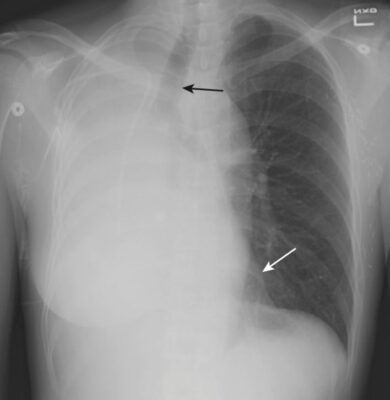

- Khi có tràn dịch hoặc tràn khí màng phổi nhiều, mất thể tích liên quan đến xẹp phổi do chèn ép có thể cân bằng với tăng thể tích do dịch (như trong tràn dịch màng phổi) hoặc khí (như trong tràn khí màng phổi). Ở một bệnh nhân người lớn bị mờ nửa phổi, không có hình ảnh phế quản chứa khí, và ít hoặc không có sự dịch chuyển của các cấu trúc lồng ngực di động, cần phải nghi ngờ một ung thư biểu mô phế quản gây tắc nghẽn, có lẽ kèm theo di căn đến màng phổi (Hình 9).

Xẹp phổi toàn bộ (xem Hình 3 và 4)

- Trên phim X quang thẳng:

- Mờ phổi xẹp do mất không khí.

- Nửa cơ hoành ở bên bị xẹp phổi sẽ bị phủ bóng bởi phổi không có thông khí phía trên nó.

- Có sự dịch chuyển của tất cả các cấu trúc di động của lồng ngực về phía bên của phổi xẹp.